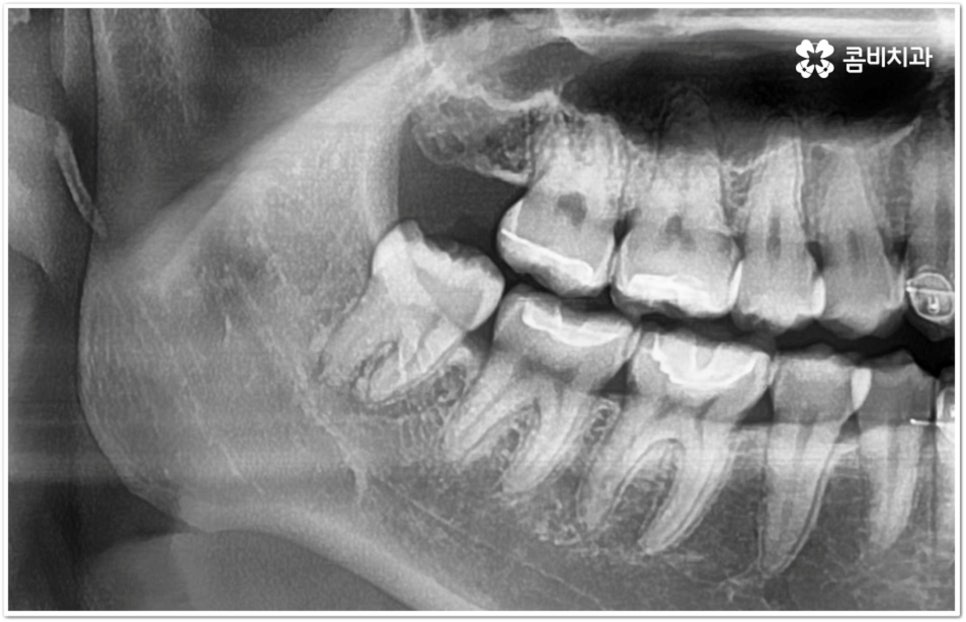

만약 똑바로 자라나고 관리가 용이하며 마주보는 대합치 역시 정상적으로 맹출되었다면 사랑니를 꼭 발치할 필요는 없을 거예요. 그러나 보통 사랑니는 사람의 치아 중에 가장 마지막에 나오는 치아라서 이미 구강 내 공간이 비좁은 상태이기 때문에 비스듬하게 자리를 잡고 일부분만 맹출이 되는 경우가 많이 있어요. 보통 머리가 앞쪽으로 기울어진 근심위로 자리잡는 케이스가 가장 많으며 그 밖에도 치아 머리가 뒤쪽으로 기울어져 있거나 혀쪽, 볼쪽으로 누운 케이스, 아예 옆으로 완전히 누운 케이스 등도 발견되고 있는데요.

잇몸에 반쯤 덮힌 채로 삐뚤게 나온 사랑니는 칫솔질을 제대로 하기 어렵고 위생 관리가 잘 되지 않아 주변 잇몸에 염증이 생기기 쉬우며 어금니까지 충치가 번질 위험이 높아지게 되어 구강 건강 관리 및 예방 차원에서 발치 처치를 해주실 필요가 있어요. 발치 난이도는 사랑니의 경사 각도와 방향 및 치아 뿌리의 길이와 개수, 사랑니 뒤쪽 턱 뼈의 각도 및 형태, 하치조 신경 또는 상악동까지의 거리 등에 따라서 달라질 수 있습니다.

이때 아래사랑니발치 의 경우 아래턱 부근을 지나가는 큰 신경인 하치조 신경을 건드리지 않고 조심스럽게 사랑니만 제거해야 하기 때문에 3D-CT 등 정밀 검진 기계를 통해 사랑니의 매복 위치, 깊이, 각도 등의 상태와 신경까지의 거리 등을 먼저 꼼꼼하게 파악한 후에 발치를 해 줄 필요가 있는데요. 만약 완전히 매복되어 있다면 사랑니 주변에 함치성 낭종이 발생할 수도 있는데 이로 인해 주변 치조골이 파괴되고 어금니 쪽으로 병변이 확산되면 결국 치아를 상실하게 되거나 턱뼈가 약해져서 작은 충격에도 부러지는 현상이 발생할 가능성도 있으므로 될 수 있는대로 치료 시기를 놓치지 않는 것이 중요한 포인트라고 할 수 있어요.

이와 같이 환자분들의 상황에 따라서 잇몸 절개 및 골삭제 후 사랑니를 조각내어 빼내야 하는 고난도의 과정들이 필요할 수도 있기 때문에 아래사랑니발치 시 관련 임상 경험이 많고 섬세한 기술력을 가지고 있는 숙련된 의료진과 함께 하시길 권유드리고 있습니다.

관리하기 까다롭기 때문에 위 아래사랑니발치 를 해 주는 것이 보통이긴 하지만 간혹 사고로 어금니를 상실하거나 유전적으로 어금니가 없으신 분들의 경우 교정 치료를 통해 어금니 대신 사용하는 사례가 있으니 필요하다면 발치 결정 전에 꼼꼼하게 검진을 받아보실 필요가 있어요.

모든 경우에 사랑니가 어금니를 대신할 수는 없으며 사랑니로 어금니를 대체하기 위해서는 사랑니의 상태, 이동 가능 공간, 주변 구조물 및 전체 구강 구조 등 환자분들의 상황을 먼저 면밀하게 살펴본 후 교정 치료 계획을 세심하게 세워 잇몸과 사랑니의 손상 없이 치료할 필요가 있으므로 고난도 과정에 맞게 술자의 높은 숙련도가 요구되는 만큼 노하우가 풍부한 의료진을 선택하시길 권유드리고 있습니다.